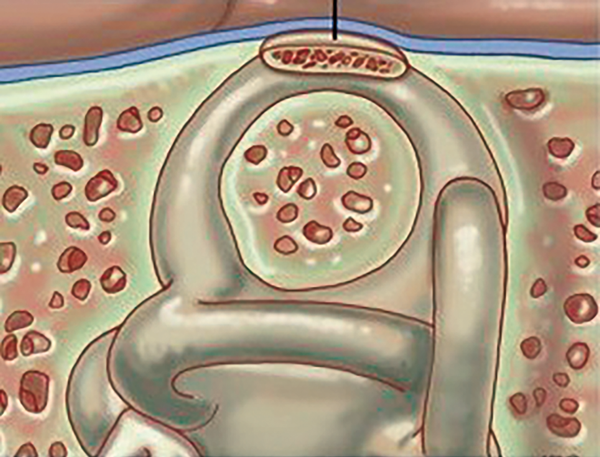

Figure 3: Top) Obliteration of the superior semicircular canal.

Bottom) Resurfacing of the superior semicircular canal.

The aim of surgery is to either cover the defect or to obliterate the SSC (Figure 3). The approach to the SSC is either through middle cranial fossa or transmastoid. Proponents of middle cranial fossa surgery argue that there is better visualisation of the arcuate eminence to confirm diagnosis and confirm coverage / closure. They also suggest that the risk of neurosurgical complications related to craniotomy and temporal lobe retraction is low. Several groups state that this is their approach of choice [6]. Alternatively, the transmastoid approach is one more familiar to otologists and avoids the risk of intracranial complications. Its main disadvantage is the visualisation of SSC along the tegmen, particularly if the tegmen hangs low. Many groups describe good success with the transmastoid approach [7, 8].

Aside from the approach, several different methods of addressing the SSC have been described. There may be a lower rate of recurrence with occlusion and resurfacing compared with resurfacing alone [2]. Some groups have, however, had good success with resurfacing alone particularly when bone pate and fascia are used to create a smooth covering over the length of the dehiscence [6]. Failures of resurfacing alone have been associated with the use of a bone plate that has dislodged with time [2]. It is possible that resurfacing does not obliterate the third window effect completely and hence some symptoms may remain.

Canal occlusion is undertaken in a similar manner to that for posterior semicircular canal occlusion used for intractable benign positional vertigo (Figure 4). The use of bone wax, bone pate and temporalis fascia have all been described although bone wax may be the most effective. The occlusion material is placed either side of the bony defect via a fenestration into the crura of the SSC. This prevents fluid movement inside the canal.